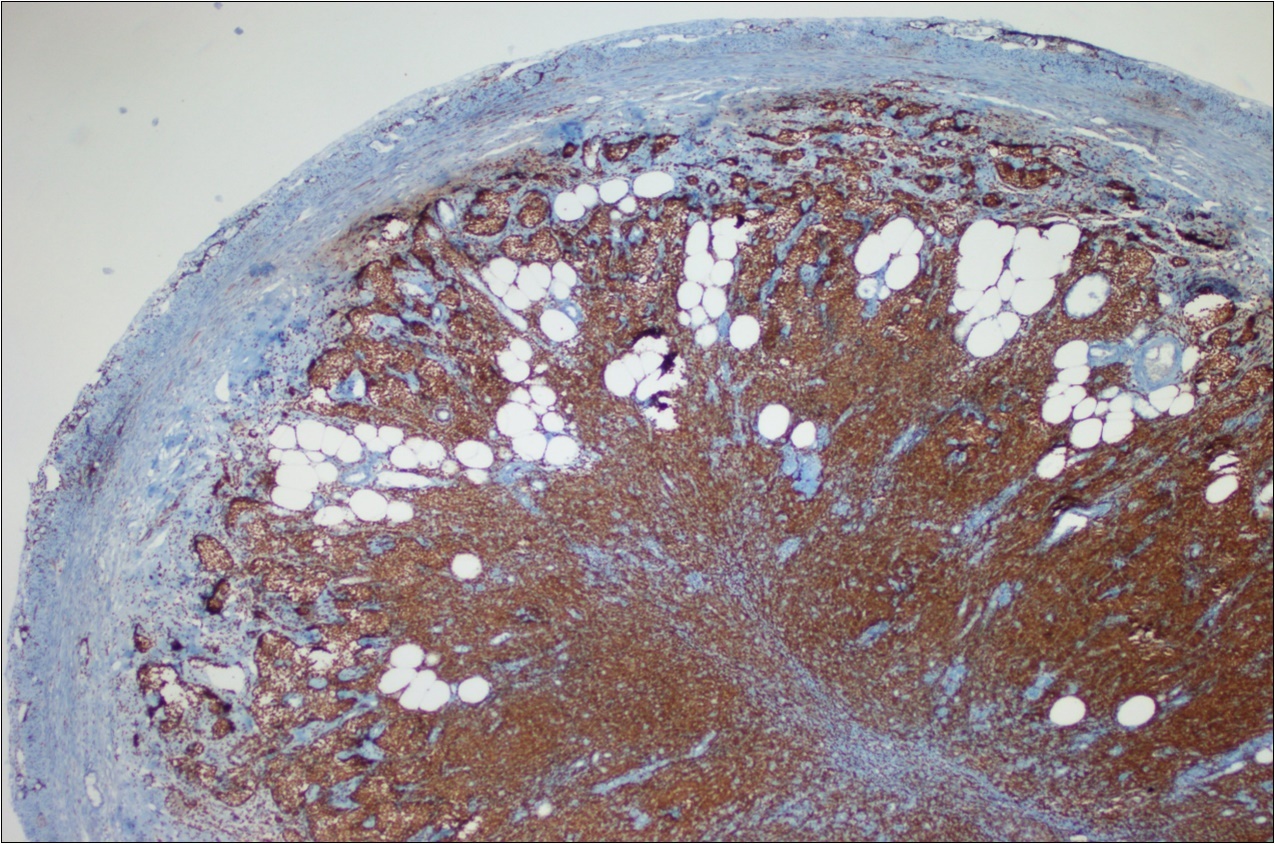

A 63-year-old woman presented to the Department of General Surgery as an outpatient with abdominal pain. Physical examination showed the signs of acute appendicitis and appendectomy was performed. During microscopic examination, a small focus of atypical monotonous lymphoid cell population was seen and the material was sampled totally. The pathological examination revealed MALT lymphoma (Figure 1), with diffuse positivity of cluster of differentiation (CD) 20 (Figure 2), CD 79a and B-cell lymphoma (Bcl- 2) (Figure 3) with just a few CD3 positive lymphoid cells. However, no evidence of adenocarcinoma was found in the appendectomy specimen. After the diagnosis of lymphoma, a complete colonoscopy was planned and this revealed a solid tumoral mass in the caecum measuring 5x4x4 cm. Computed tomography of the abdomen and pelvis revealed mesenteric lymphadenopathy associated with a mass in the caecum with multiple nodules in liver consistent with metastasis (Figure 4). Frozen sections were not obtained since the treatment method would not be affected. The patient underwent anterior resection with regional lymphadenectomy, with the pathological assessment of the resected specimen revealing a collision tumor consisting of a poorly differentiated adenocarcinoma extending through the muscularis propria with MALT lymphoma (Figure 5). Microscopic evaluation of the 11 regional lymph nodes in the mesentery of the resected colon and liver biopsy showed diffuse infiltration of MALT lymphoma with metastasis of adenocarcinoma (Figure 6). According to immunohistochemistry, atypical lymphocytes were positive for CD 20, Bcl-2, and negative for CD3, CD5, CD10, CD23, Bcl-6, terminal deoxynucleotidyl transferase, and cyclin D1. The proliferation fraction (MIB-1 immunostaining) was approximately 20%. The morphological and immunohistochemical findings were used to confirm the diagnosis of synchronous presentation of MALT lymphoma and colon adenocarcinoma within the caecum, mesenteric lymph nodes and liver metastases.

Figure 2.CD 20 positivity of lymphoid cells (CD20, x200)

Figure 3.Bcl-2 positivity of lymphoid cells (Bcl-2, x200)